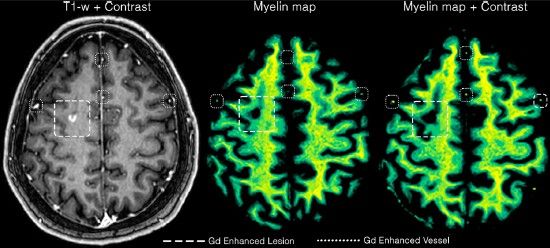

onlinelibrary.wiley.com/doi/full/10....

#neuroimaging #neurology #neuroskyence #radiology #syntheticmri #gadolinium #quantification

Free read

onlinelibrary.wiley.com/doi/full/10....

#neuroimaging #neurology #neuroskyence #radiology #syntheticmri #gadolinium #quantification

Free read